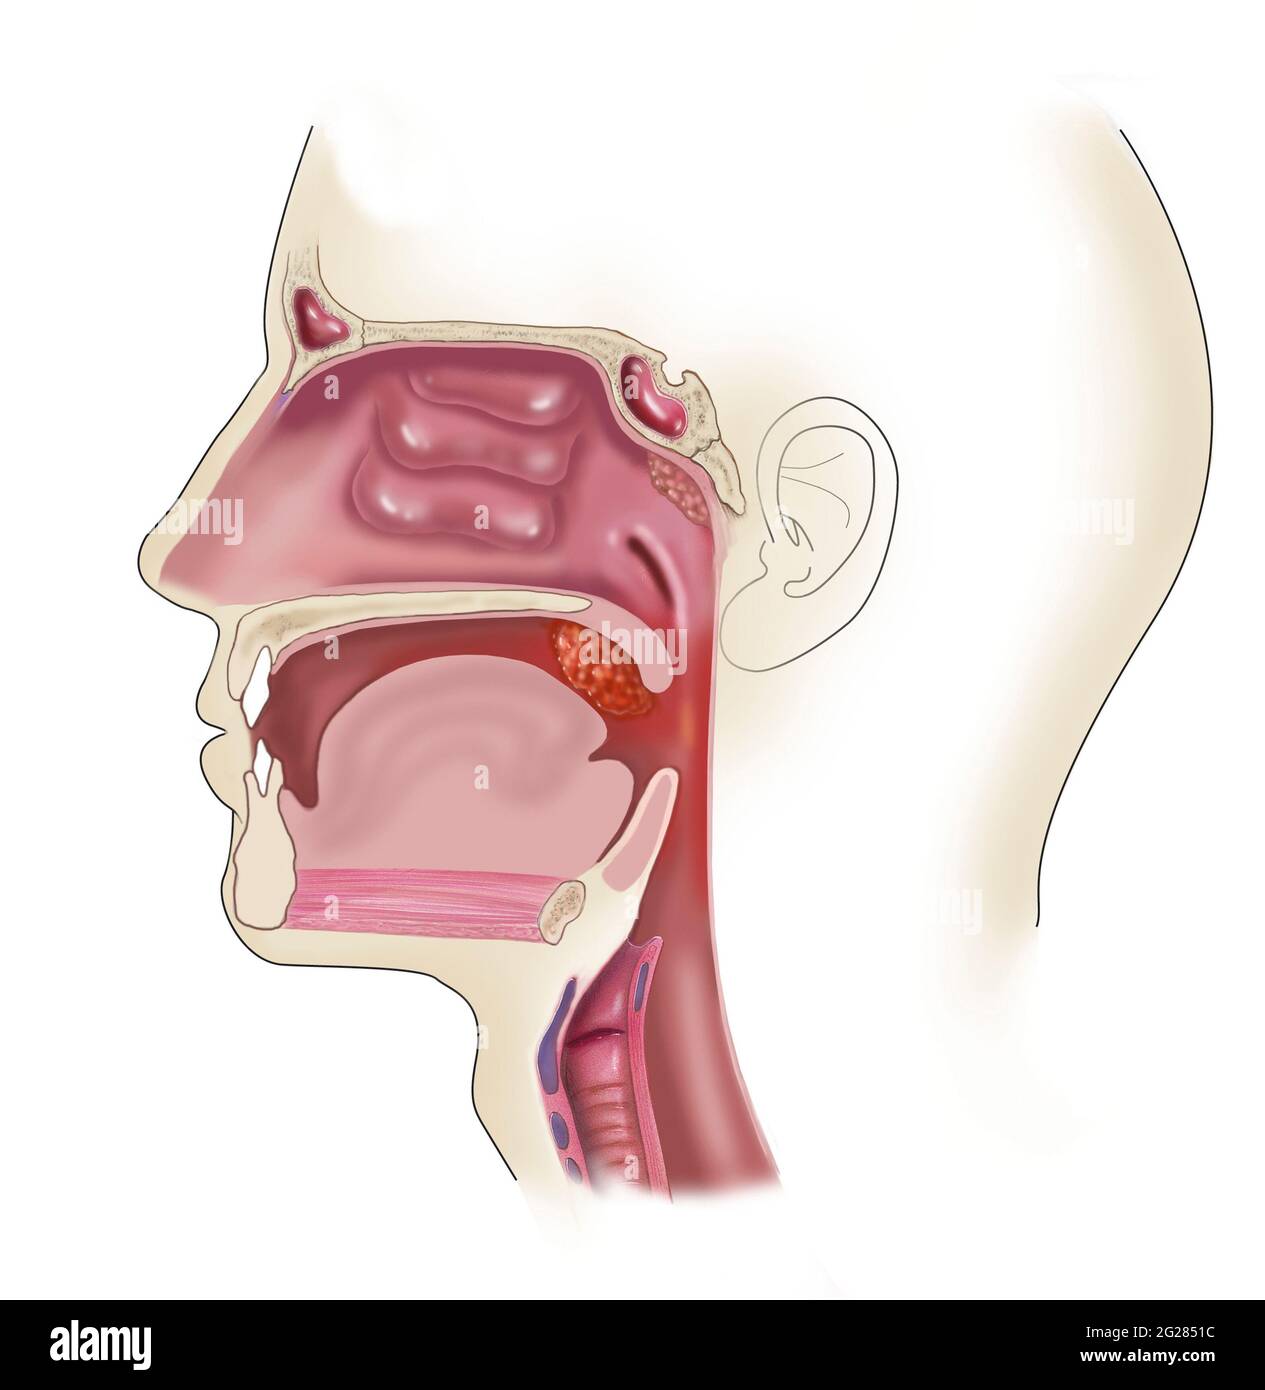

Seitenansicht des Kopfes, wo sich geschwollene und vergrößerte Mandeln befinden. Stockfotohttps://www.alamy.de/image-license-details/?v=1https://www.alamy.de/seitenansicht-des-kopfes-wo-sich-geschwollene-und-vergrosserte-mandeln-befinden-image431667785.html

Seitenansicht des Kopfes, wo sich geschwollene und vergrößerte Mandeln befinden. Stockfotohttps://www.alamy.de/image-license-details/?v=1https://www.alamy.de/seitenansicht-des-kopfes-wo-sich-geschwollene-und-vergrosserte-mandeln-befinden-image431667785.htmlRF2G284JH–Seitenansicht des Kopfes, wo sich geschwollene und vergrößerte Mandeln befinden.

Seitenansicht des Kopfes, wo sich geschwollene und vergrößerte Mandeln befinden. Stockfotohttps://www.alamy.de/image-license-details/?v=1https://www.alamy.de/seitenansicht-des-kopfes-wo-sich-geschwollene-und-vergrosserte-mandeln-befinden-image431668088.html

Seitenansicht des Kopfes, wo sich geschwollene und vergrößerte Mandeln befinden. Stockfotohttps://www.alamy.de/image-license-details/?v=1https://www.alamy.de/seitenansicht-des-kopfes-wo-sich-geschwollene-und-vergrosserte-mandeln-befinden-image431668088.htmlRM2G2851C–Seitenansicht des Kopfes, wo sich geschwollene und vergrößerte Mandeln befinden.